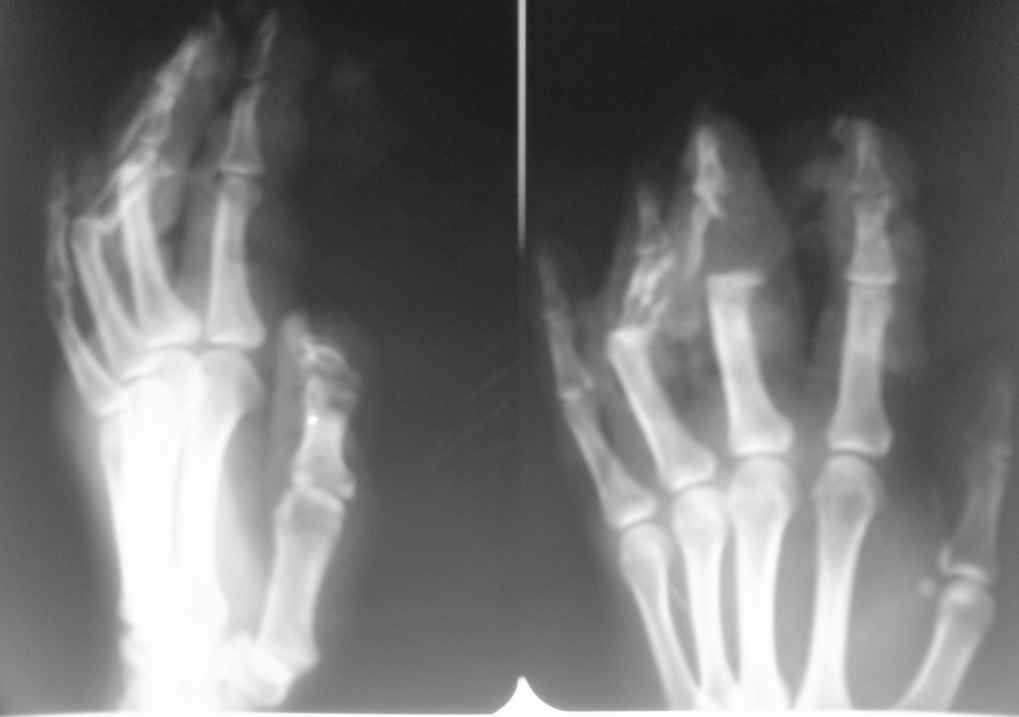

Пациентка 32 лет, врач-гинеколог. Травма электрорубанком 31.08.08

Диагноз: открытый оскольчатый перелом средних фаланг 3-4 пальцев левой

кисти, травматический дефект средней фаланги 3-4 пальцев.

<br>Травматический дефект кожи и сухожилий разгибателей 2,3,4 пальцев.

При поступлении выполненно ПХО ран, фиксация фаланг спицами в

положении разгибания, синдактилия. Пласитка кожного дефекта

полнослойным мостовидным лоскутом. Заживление ран первичное. Лоскут

жизнеспособен.